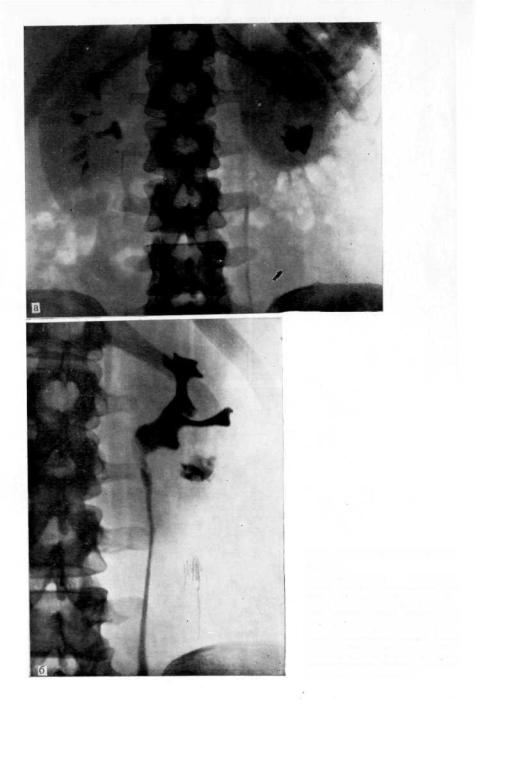

Экскреторная урография при нефроптозе: диагностические изображения